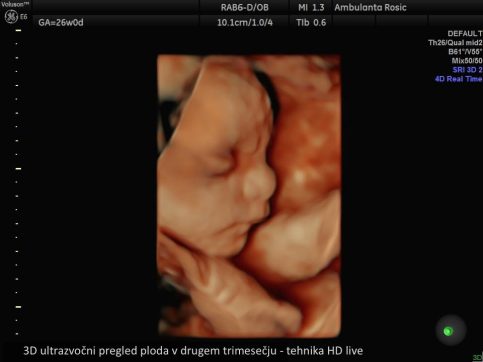

V sklopu 3D/4D ultrazvoka ploda je preiskavo mogoče opraviti tudi v tehniki HD live, pri kateri lahko s pomočjo posebnih tehnik osvetljevanja, senčenja ter virtualnega izvora svetlobe plod prikažemo neverjetno realistično.